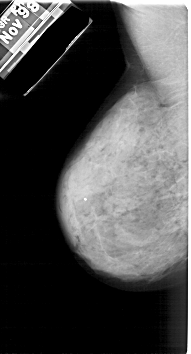

A_1874_1.LEFT_MLO

LEFT_MLO LINES 5296 PIXELS_PER_LINE 2851 BITS_PER_PIXEL 12 RESOLUTION 43.5 NON_OVERLAY